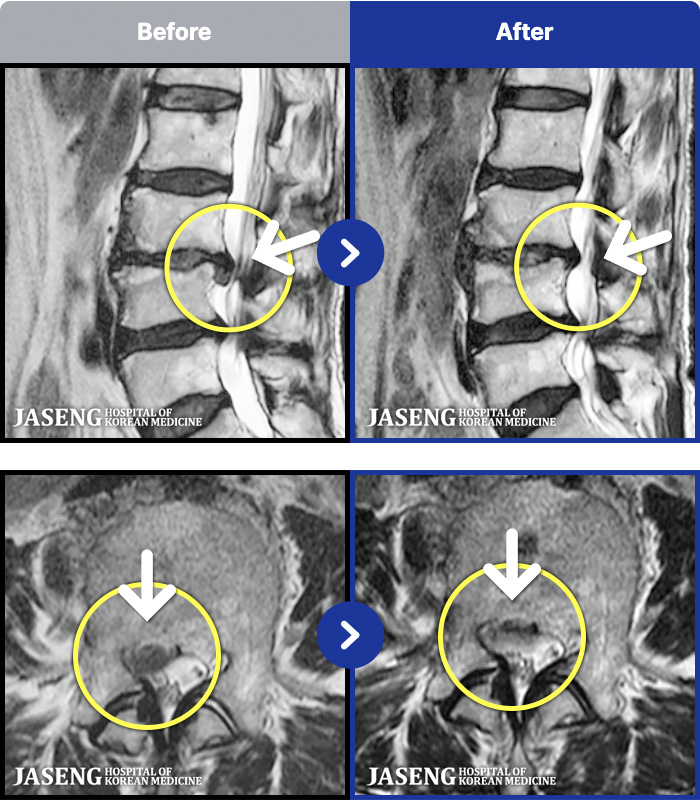

ȯںп Ǹ ǿ ԿǾ, ο ġ ۿ Ƿ ġḦ Ͻñ ٶϴ.